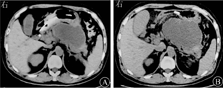

入院后查血常规示白细胞计数为17.5×109/L,红细胞计数为5.87×1012/L,血红蛋白为185 g/L,中性粒细胞占比为0.83,血细胞比容为0.54;血清甘油三酯为4.09 mmol/L,血肌酐为161 μmol/L(正常参考值为57~97 μmol/L),血钙为2.33 mmol/L,血淀粉酶为959 U/L,ALT和AST均为16 U/L;CRP为418 mg/L,血降钙素原为0.08 μg/L;凝血功能示血浆D-二聚体为0.95 mg/L,纤维蛋白降解产物为7.40 mg/L,PT为14.3 s;血气分析示pH值为7.339,动脉血氧分压为8.64 kPa,二氧化碳分压为5.41 kPa;心肌酶谱示肌红蛋白为167.8 μg/L,高敏肌钙蛋白I为1.490 μg/L,入院后2 d复查血肌酐为336 μmol/L。心电图检查示窦性心动过速,广泛T波低平。2019年10月16日中腹部CT平扫检查示胰腺假性囊肿形成(图1A),10月29日腹部CT平扫检查示SAP,胰腺假性囊肿较前增大,囊肿最大径约为12 cm,且囊肿壁包裹完整并紧贴胃壁,无合适经皮穿刺路径(图1B)。

图1 中腹部计算机断层扫描平扫检查结果

A 2019年10月16日(发病3周)检查结果示胰周假性囊肿形成 B 2019年10月29日(发病4周)检查结果示胰周假性囊肿增大